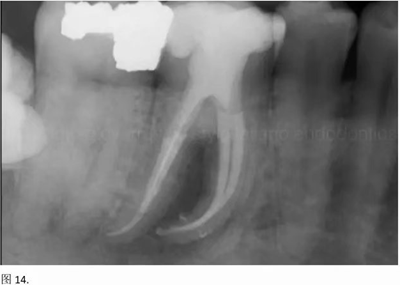

本文的目的是描述一種旨在優(yōu)化根管根尖部分預備的預敞技術。根管頸部或冠方的早期預敞對于減少初尖銼直徑和根尖部根管直徑之間的差異至關重要。大量研究表明,手用或機用器械預敞根管能顯著減少器械折斷的發(fā)生率。